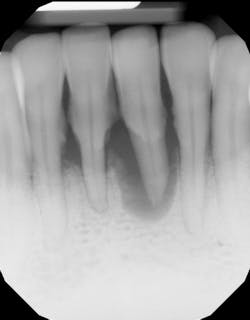

- Proper surgical technique including incision, flap design, and complete detoxification of bony defect and root apices (figures 3 and 3a)